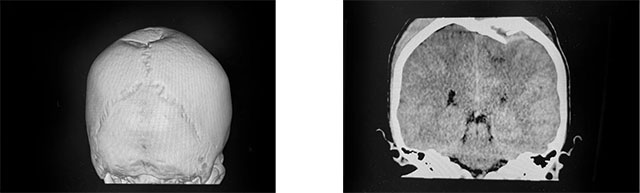

▲ CT影像顯示,小寶頂骨大塊凹陷性骨折,腦頂葉皮層受壓

小寶被收治入院后,神經外科6A病區(qū)醫(yī)生團隊第一時間為患者開展了全面的檢查,并采取了降顱壓等治療措施。CT檢查報告很快出來了,患者兩側頂骨(左側為主)大塊凹陷性骨折(約5cm*6cm),下陷約2cm,腦頂葉皮層受壓、凹陷,骨折區(qū)域硬膜外、腦表急性期血腫,左側幕上輕度高顱壓。由于損傷部位涉及腦部重要功能區(qū),需通過手術,減輕顱骨骨折壓迫,清除顱內血腫并修復受損的顱骨,防止可能出現(xiàn)的腦神經功能損傷。